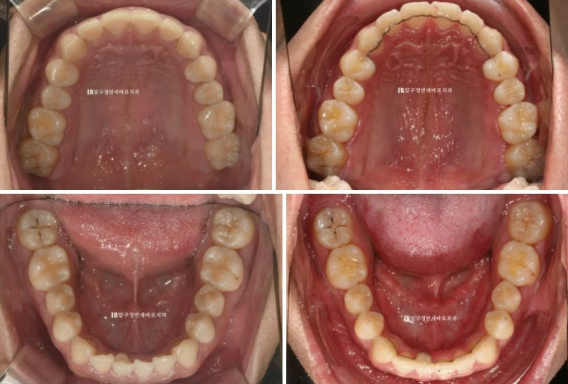

윗니는 가지런했지만

24.02

아래 앞니 하나가 삐뚤합니다.

특히 아래 앞니 중 하나에 기형치도 보입니다.

뒤쪽으로 튀어나온 부분은 치아의 일부 입니다.

24.02~24.07

과개교합이 해소가 되면서 이제는 다물었을 때 아랫니도 보입니다.

삐뚤했던 앞니가 가지런해지고, 아래 앞니 기형치 부분은 그에 맞게 철사 유지장치가 제작이 되었습니다.